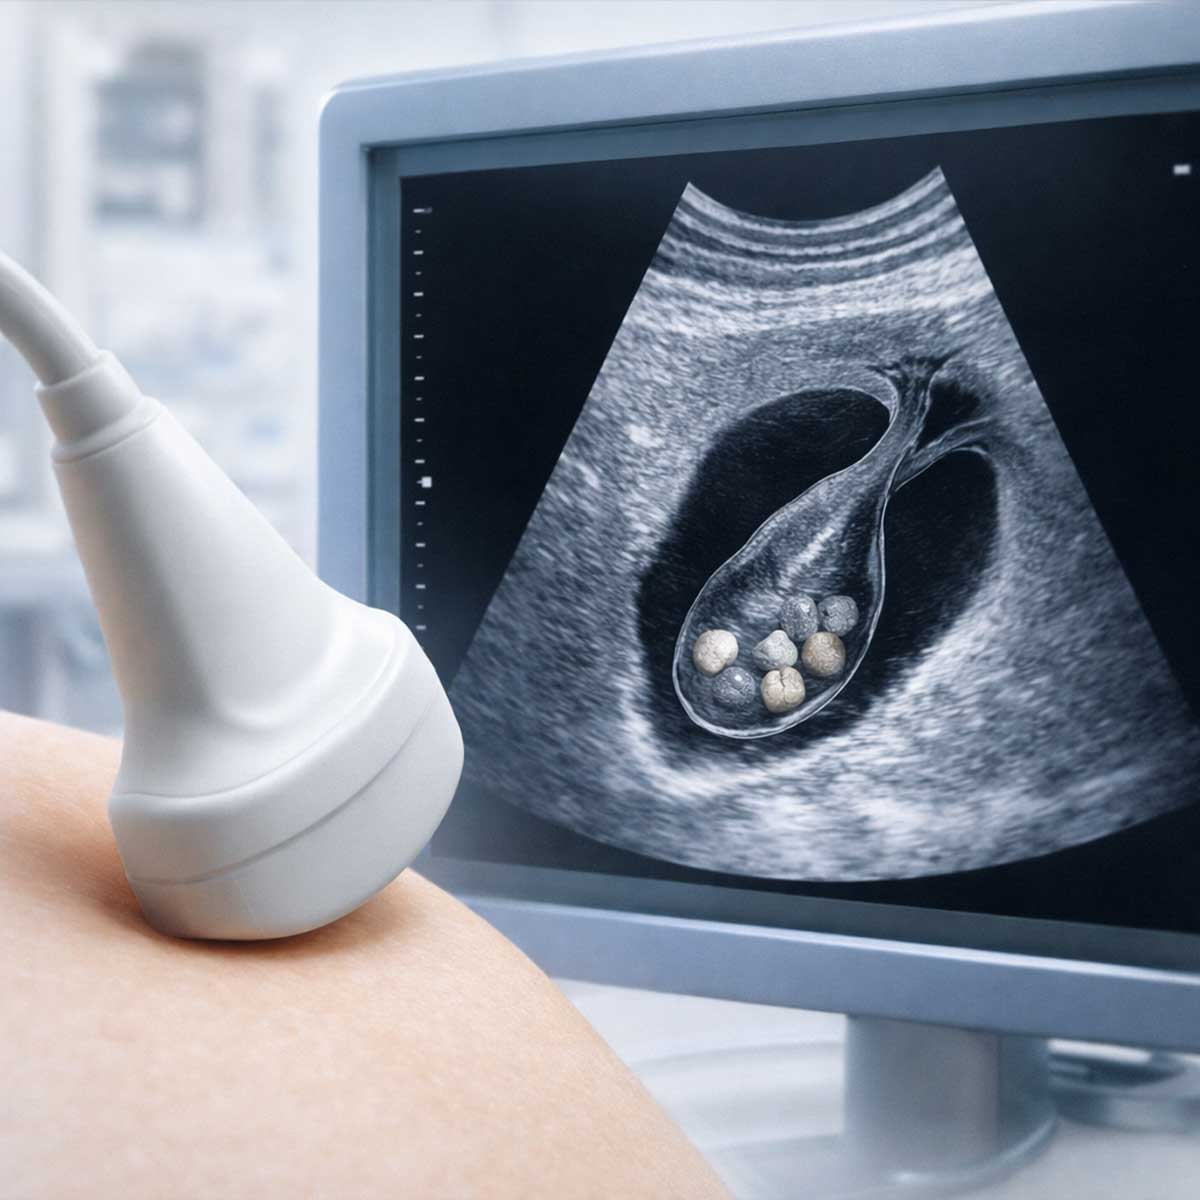

Ультразвуковое исследование — основной и наиболее доступный метод диагностики желчнокаменной болезни. Именно с УЗИ обычно начинается обследование при подозрении на ЖКБ.

Исследование проводится натощак, что позволяет получить наиболее точные результаты. УЗИ безопасно, не связано с лучевой нагрузкой и может выполняться повторно при необходимости.

По словам врача-гастроэнтеролога, регулярное УЗИ при наличии факторов риска позволяет вовремя выявлять камни и предотвращать осложнения.

| УЗИ желчного пузыря | Камни, их размер и количество, состояние стенок желчного пузыря, застой желчи | Первый и основной метод диагностики при подозрении на ЖКБ |